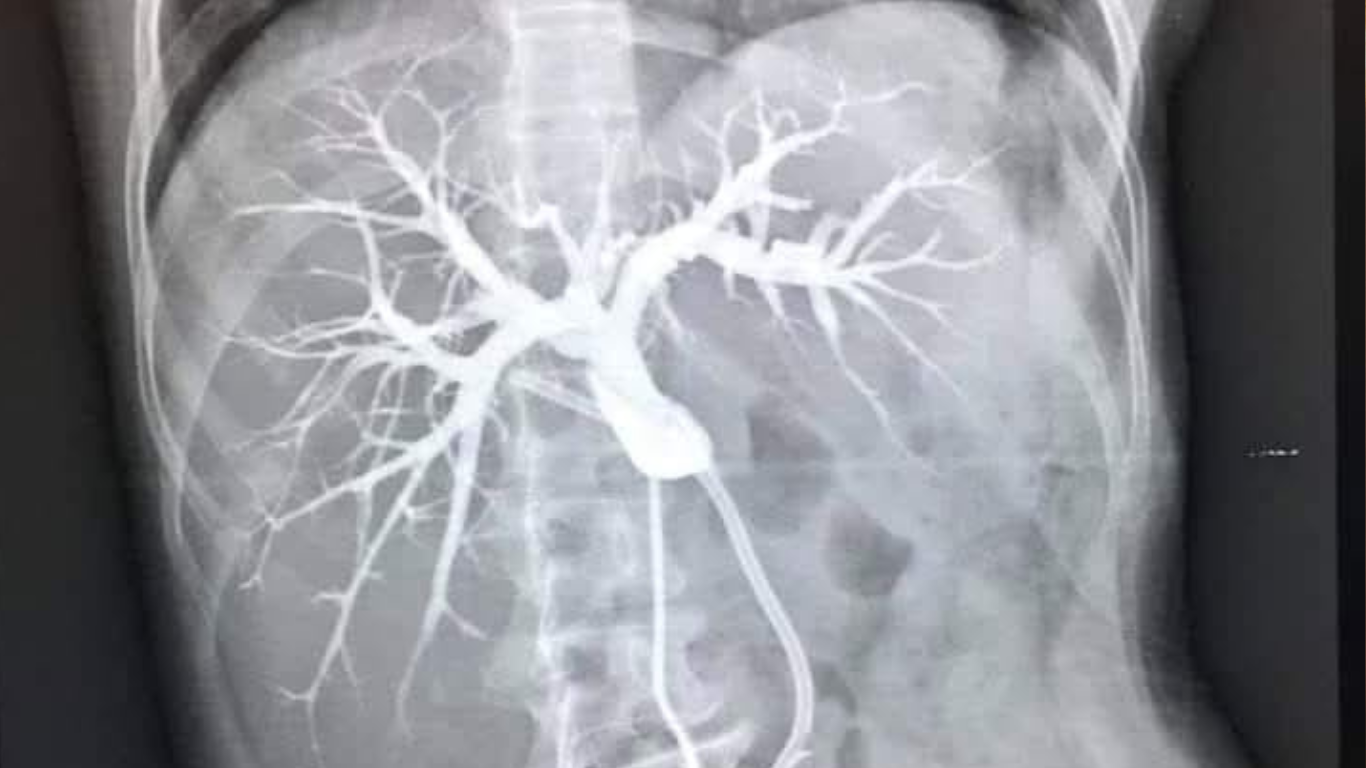

A colangiopancreatografia é um estudo diagnóstico voltado para a visualização dos ductos biliares e pancreáticos, utilizando diferentes técnicas que combinam endoscopia e radiografia.

Ao aprofundarmos neste tema, podemos distinguir entre dois métodos principais: a Colangiopancreatografia Endoscópica Retrógrada (CPER) e a Colangiopancreatografia por Ressonância Magnética (CPRM).

Enquanto a CPER é um procedimento invasivo, que requer sedação e possibilita intervenções terapêuticas diretas, a CPRM é uma modalidade não-invasiva, servindo principalmente para fins diagnósticos.

Um corante é injetado, permitindo capturas de imagens detalhadas através de radiografias. A CPRM, por outro lado, utiliza a tecnologia de ressonância magnética para criar imagens detalhadas sem a necessidade de um procedimento invasivo.